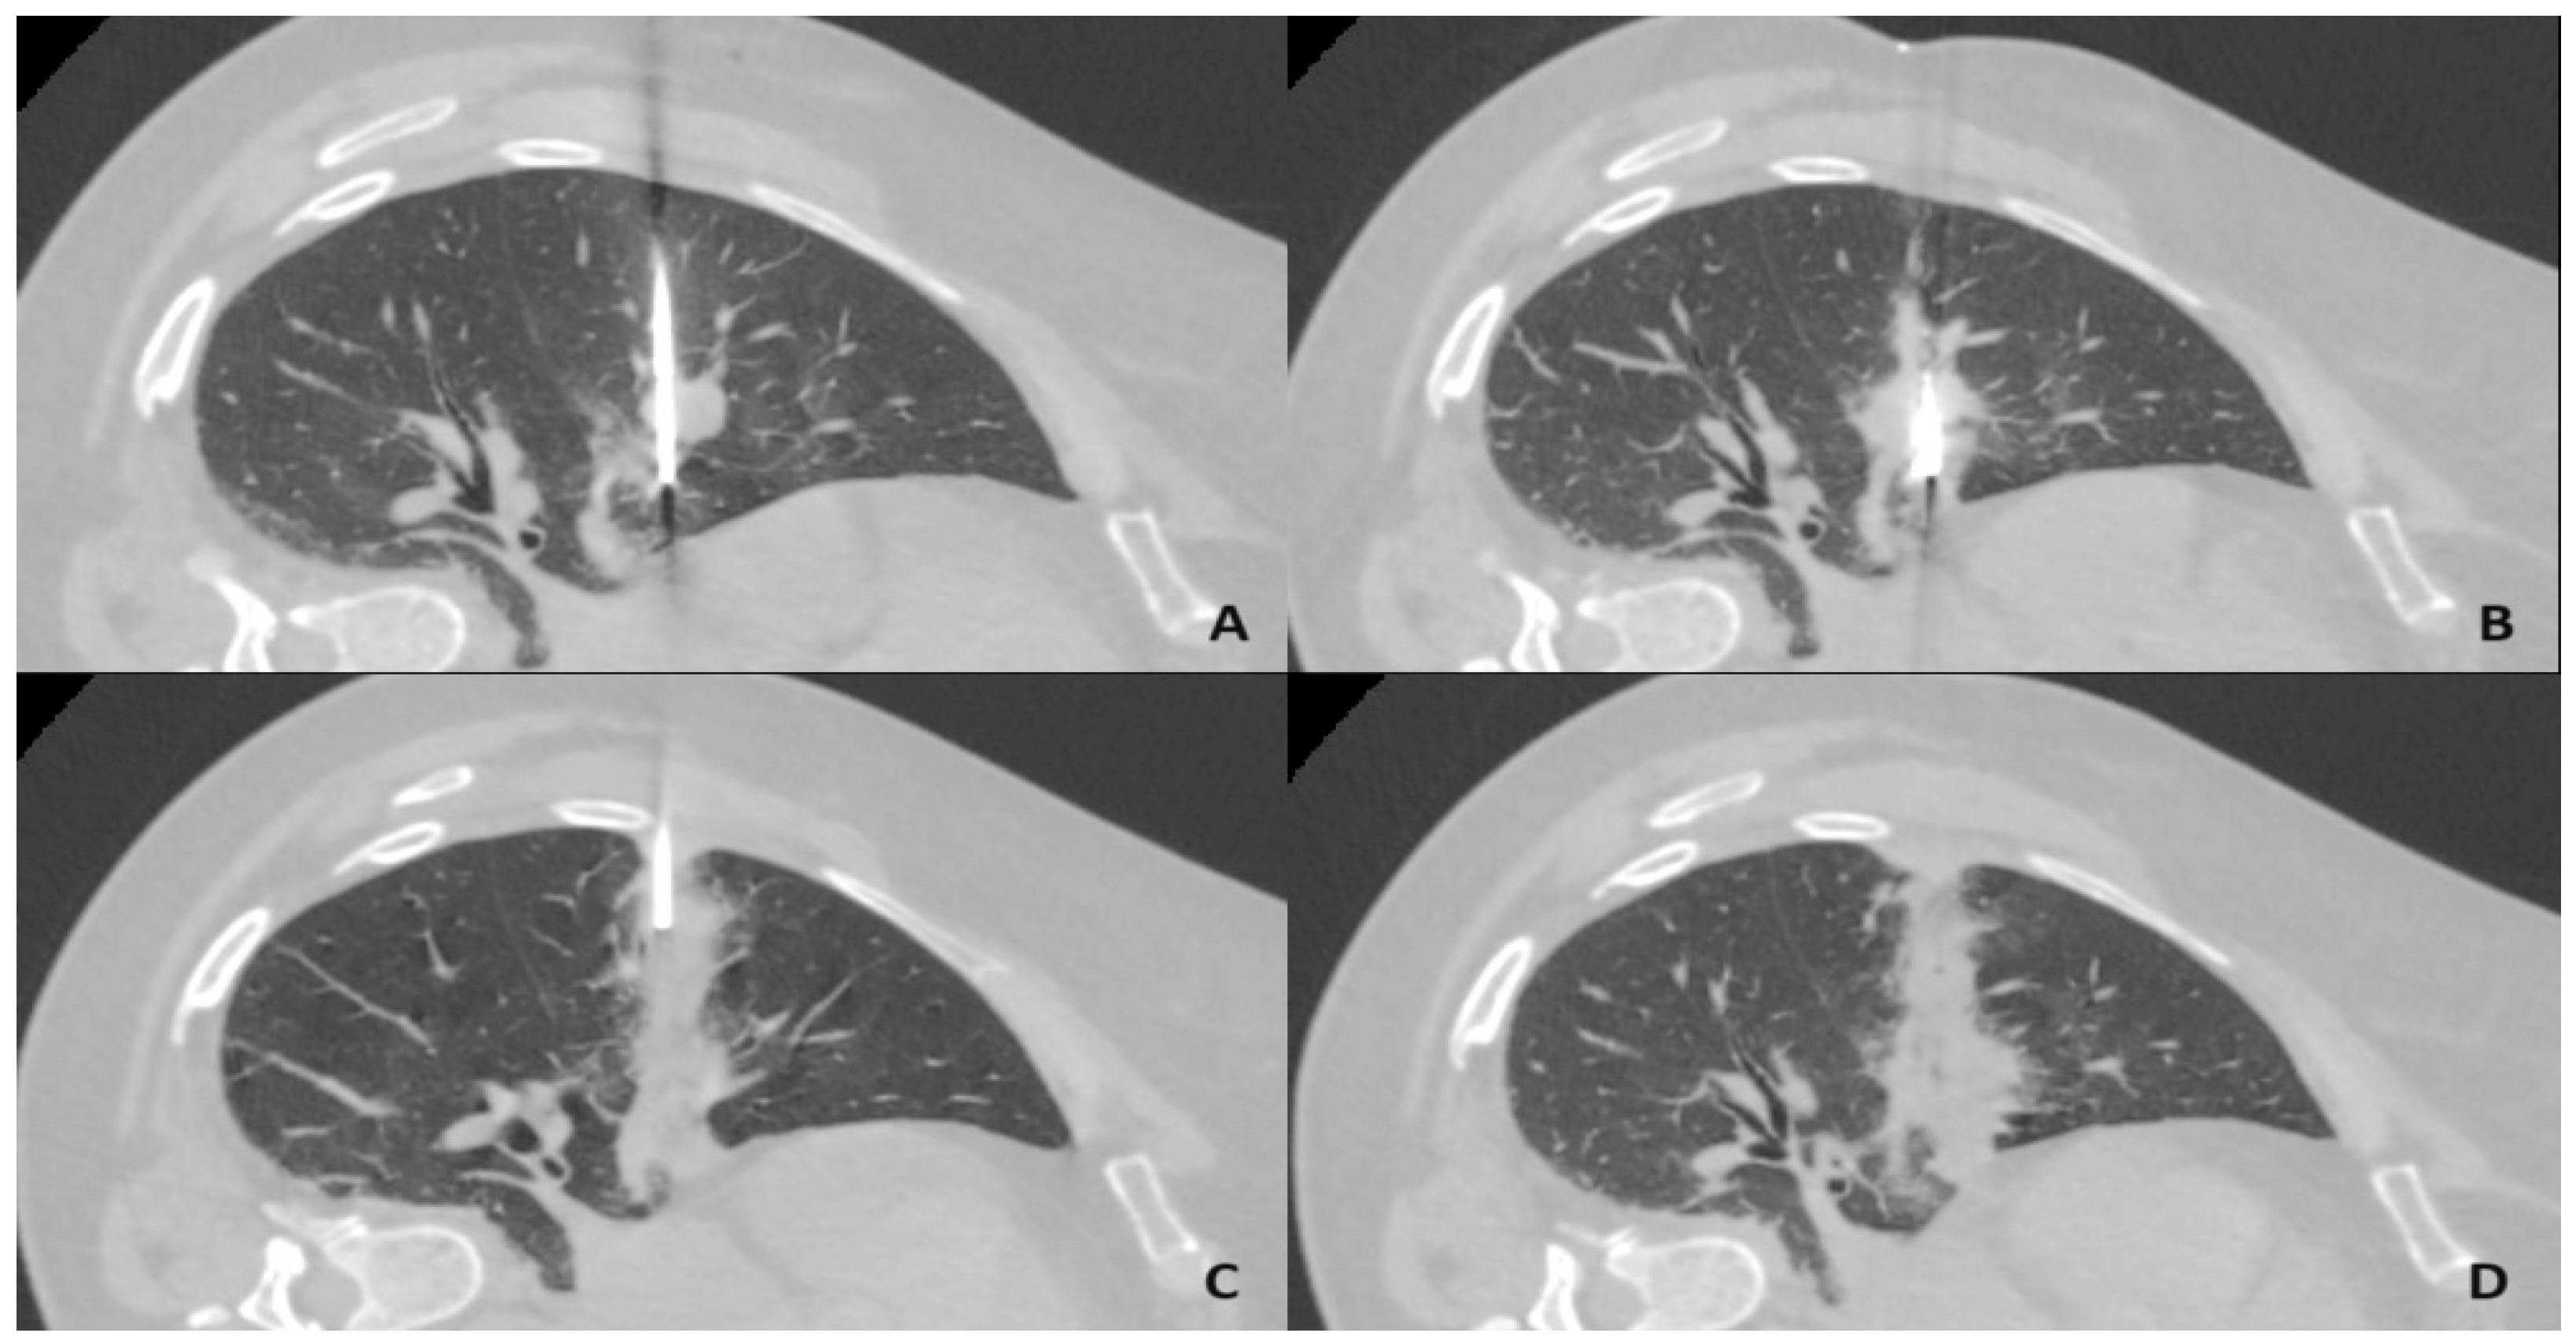

1. Introduction

2. Materials and Methods

2.2. Microwave Ablation Procedure

2.3. Tract Sealing Using an Autologous Venous Blood Clot